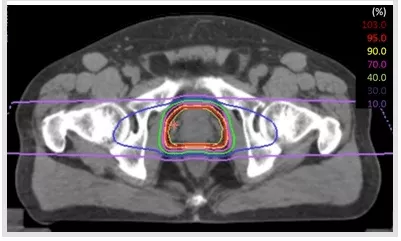

放射治療是前列腺癌具有代表性的非手術(shù)治療和治愈性治療,尤其對于老年患者具有重要意義。

但是傳統(tǒng)的光子放療會導(dǎo)致直腸和膀胱不良事件的產(chǎn)生,不利于前列腺癌患者生活質(zhì)量的提升。與傳統(tǒng)的光子放療不同,質(zhì)子治療及重離子治療這兩種新興的放療手段在人體內(nèi)會產(chǎn)生“布拉格峰效應(yīng)”,簡單說就是進(jìn)入人體時能量小,達(dá)到腫瘤處能量突然暴增,因此對正常組織損傷非常小。相比傳統(tǒng)的光子放療,質(zhì)子重離子治療前列腺癌的效果更加顯著,且減少了膀胱、直腸和陰莖球的輻射劑量,副作用更低。